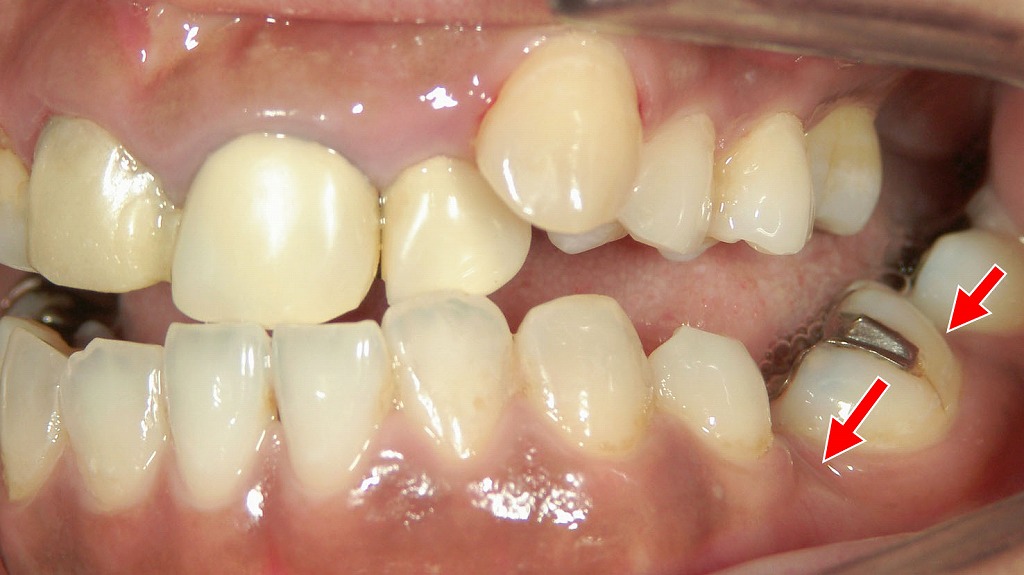

5番抜歯後のブリッジが原因で4番に負担集中:歯根破折の典型例

5番を抜歯後、4・5・6番でブリッジを装着した症例です。欠損部を支えるため4番に大きな咬合負担がかかり、赤矢印の歯が“歯根破折”を起こしてしまいました。ブリッジは見た目も噛み心地も自然ですが、支えとなる歯に過重負担がかかるリスクがあります。特に小臼歯の支台歯は破折しやすく、治療選択時の重要なポイントとなります。